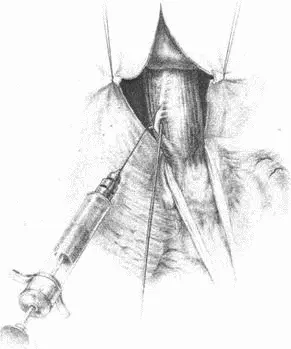

Рис. 71.Тотальная гастрэктомия. Треугольная связка левой доли печени

Рис. 72.Пересечение венечной связки при мобилизации левой доли

Рис. 73.Обкалывание нижней диафрагмальной вены

Рис. 74.Рассечение диафрагмы между двумя лигатурами

Рис. 75.Сагитальная диафрагмотомия. Мобилизован пищевод

Рис. 76.Сагитальная диафрагмотомия. Анестезия и пересечение левого блуждающего нерва

Рис. 77.Сагитальная диафрагмотомия. Пересечение левого блуждающего нерва

Рис. 78.Рассечение серозного покрова тонкой кишки, указывающего место наложения швов-держалок, и наложение первого шва на тощую кишку и пищевод